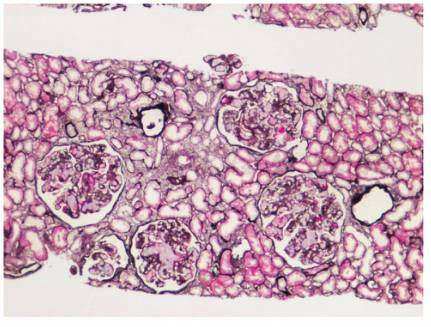

肾穿刺活检:免疫荧光,免疫球蛋白和补体均阴性。光镜:肾小球毛细血管袢高度扩张,扩张的管腔内充填栓子样细泡状蛋白物质(图1),油红 O染色阳性(图2)。

图1 脂蛋白肾病:肾小球毛细血管袢扩张,充以浅染的栓子样蛋白(PASM×100)

1.肾组织活检病理的特殊表现 光镜下肾小球毛细血管袢高度扩张,扩张的管腔内充填染色浅淡的网状物质,油红O染色阳性。